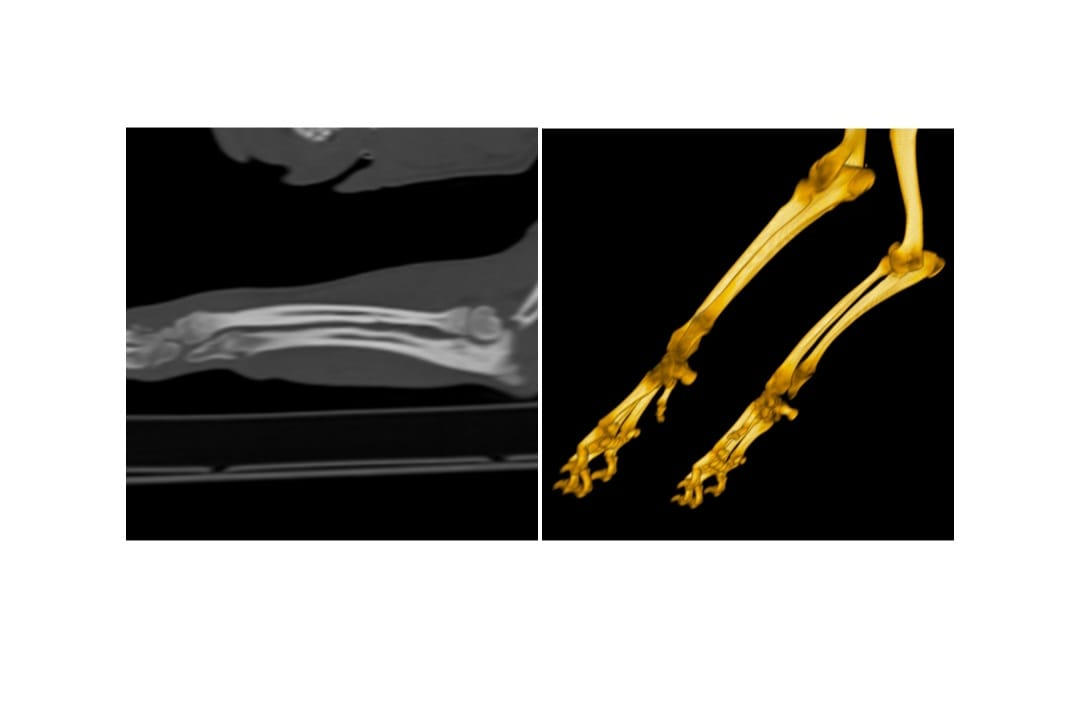

Radiographic exam and CT scan of forelimbs was performed

Diagnostic imaging reveal bone density alterations affecting the distal ulnar physis, bilaterally, characterized by bone rarefaction, retention of the cartilaginous core and irregular ossification.

ct scan retained ulnar cartilage core

(CT scan image:

courtesy of TcVet Milano Centro,

Advanced Imaging Diagnostic Center)